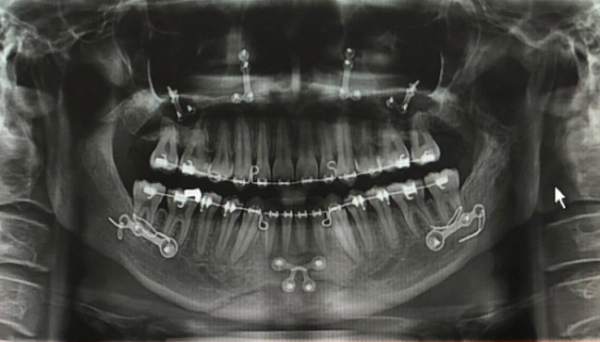

악(顎)교정술(턱의 위치나 모양을 변형시키는 수술)의 일종으로 윗턱인 상악(上顎)과 아랫턱인 하악(下顎)을 함께 수술하는 경우 양악(兩顎)수술이라 칭한다. 쉽게 말해 코 밑부터 아래턱 뼈 부분을 잘라내서 턱을 축소시켜, 얼굴을 바꾸는 치과 영역의 대수술.

양악수술을 하는 방법은 상악과 하악의 뼈를 잘라서 2개로 분리한 다음 정상 교합에 맞게 상악과 하악의 뼈를 이동시키고 이동된 뼈를 고정하는 방법이다. 뼈를 이동하는 대수술인 만큼 수술은 전신마취로 진행되며 보통 3일~7일 정도 입원하게 된다.

이렇게 대수술을 거치고 난 이후 해외 환자의 모습은 이렇다.

양악수술 한 사람의 엑스레이 상태